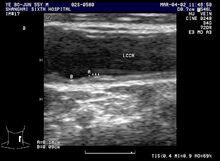

中層厚度

頸動脈內膜局部增厚系指頸動脈內膜管腔面與外膜分界面之間的距離。臨床上通過彩色都卜勒超聲診斷儀檢查頸動脈內膜中層厚度(IMT)來確定是不是有動脈粥樣硬化斑塊形成。目前認為正常IMT值應小於1.0毫米,IMT在1.0至1.2毫米之間為內膜增厚,1.2至1.4毫米之間為斑塊形成,IMT大於1.4毫米為頸動脈狹窄。